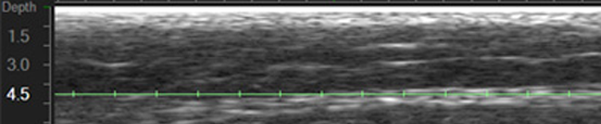

4.5 숫자 옆에 있는 녹색 가로선이 울쎄라가 작용하는 위치이고

녹색 선에 닿아있는 하얀 선이 근막입니다.

이렇게 되었을 때 제대로 된 한 샷인데요.